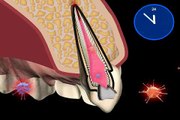

wsr ist die abkürzung für wurzelspitzenresektion. ein chirurgischer eingriff, der in der regel nichts bringt https://www.youtube.com/channel/UCtfezrProo8WbGBSwaEOMIA/search?query=wsr

im kapitalistischem medizin geschäft eingebettet, empfiehlt der kieferchirurg eben was er kann und was geld bringt ... aber nicht was gut ist für den patienten ...